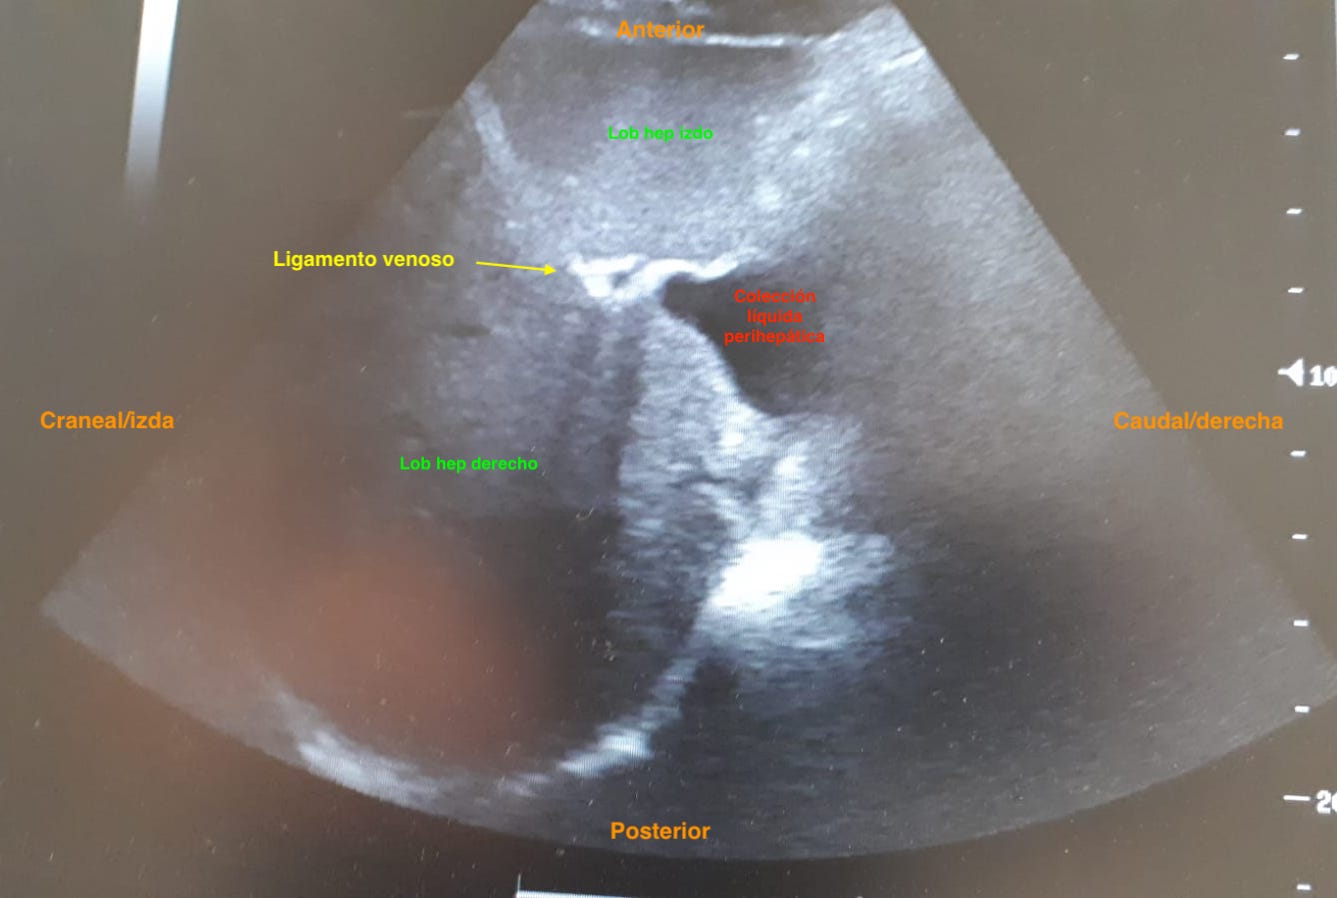

Hallazgos ecográficos

Colección líquida bien definida localizada posteriormente a lóbulo hepático izquierdo, adyacente a vena cava. Líquido peritoneal en fosa ilíaca derecha y flanco derecho, a nivel inferolateral de RD, espacio de Morrison conservado. Cantidad moderada de líquido en la pelvis.

• ECO ABD: Persistencia liquido perihepático.